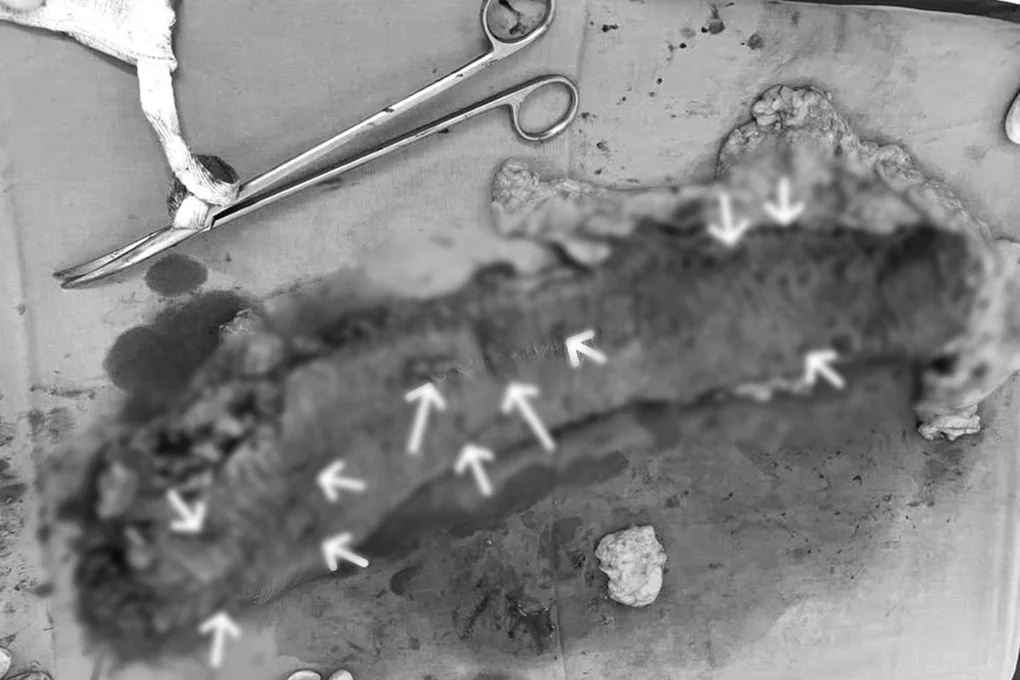

Đại tràng phải của bệnh nhân được cắt đi, ghi nhận các khối u và polyp rải rác (Ảnh: BV).

“Ca mổ kéo dài 2 giờ diễn ra thuận lợi, chúng tôi phát hiện khối u dạng sùi tại manh tràng đã gây lồng ruột, cùng với đó là một số polyp ở đại tràng phải và đại tràng ngang. Tất cả các tổn thương đều được lấy bỏ và gửi giải phẫu bệnh để đánh giá nguy cơ ung thư”, bác sĩ Phong chia sẻ thêm.